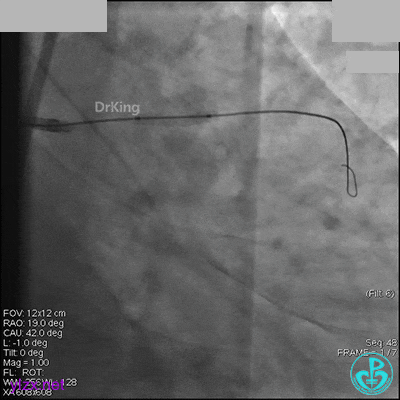

右冠脉中段充分扩张后欲植入3.5×38mm支架时,支架难以通过中远段扭曲处,且指引导管、导丝弹出飞扬。反复尝试导丝重新到达右冠脉远端时通过不顺利,局部造影剂滞留,远端血流接近3级。

右冠脉血流3级,患者无症状,终止手术。